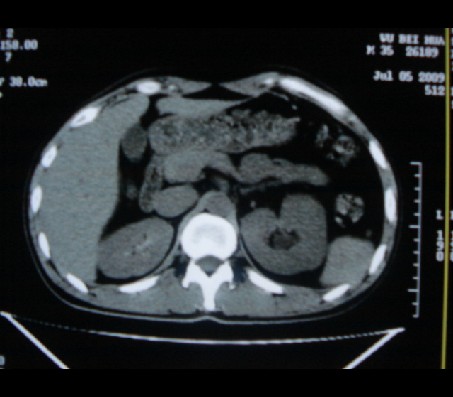

标题: CT20935:左肾占位,请会诊!

男性,35岁,ct号26189,左侧腰痛并血尿一天入院。

肾癌侵犯肾盂,肾盂出血,肾盂内为血肿

首先考虑恶性肿瘤性病变,考虑左肾癌可能性大,建议增强扫描。